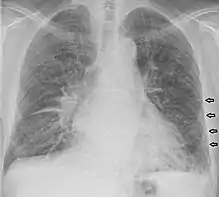

Kerley lines are a sign seen on chest radiographs with interstitial pulmonary edema. They are thin linear pulmonary opacities caused by fluid or cellular infiltration into the interstitium of the lungs. They are named after Irish neurologist and radiologist Peter Kerley.[1][2]

Kerley B lines

These are short parallel lines at the lung periphery. These lines represent interlobular septa, which are usually less than 1 cm in length and parallel to one another at right angles to the pleura. They are located peripherally in contact with the pleura, but are generally absent along fissural surfaces. They may be seen in any zone but are most frequently observed at the lung bases at the costophrenic angles on the PA radiograph, and in the substernal region on lateral radiographs.[3] Causes of Kerley B lines include pulmonary edema, lymphangitis carcinomatosa and malignant lymphoma, viral and mycoplasmal pneumonia, interstitial pulmonary fibrosis, pneumoconiosis, and sarcoidosis. They can be an evanescent sign on the chest x-ray of a patient in and out of heart failure.